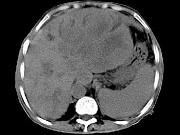

问题 女,73岁,中上腹痛1月余,患者黄疸、消瘦,CT检查如下图,最可能的诊断是()

选项 A.肝脓肿 B.巨块型肝癌 C.肝血管瘤 D.肝淋巴管瘤 E.肝胆管细胞癌

答案 B